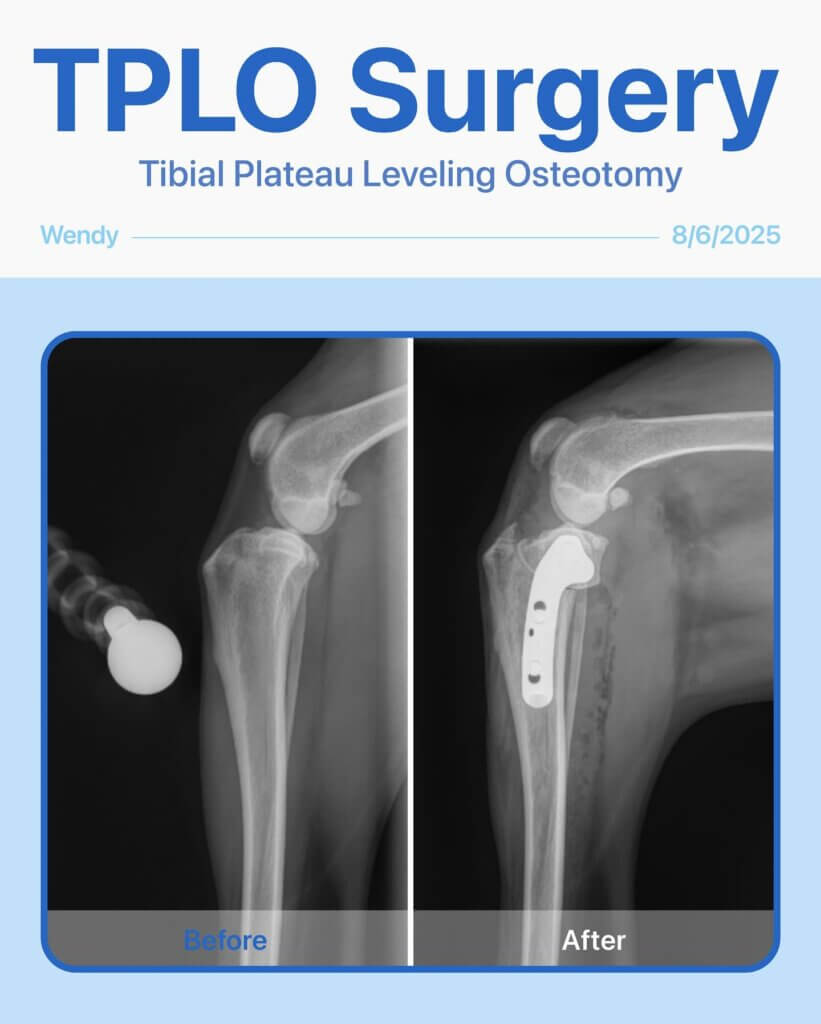

Stronger Than Ever: Wendy’s Story. Last year, Wendy, our brave 7-year-old English Shepherd, had a TPLO surgery on her back left leg. Recently, her back right leg started limping, and after a careful exam, we found that she needed another TPLO surgery.

Did you know? Dogs who experience a Cranial Cruciate Ligament (CCL) rupture in one leg have a 22–30% chance of the other leg rupturing within a few years. Wendy’s case is a reminder that even the strongest pups sometimes need a little extra care.

The surgery went smoothly, and Wendy is now on the road to recovery, already showing her resilience and happy spirit. We’re so proud of her!